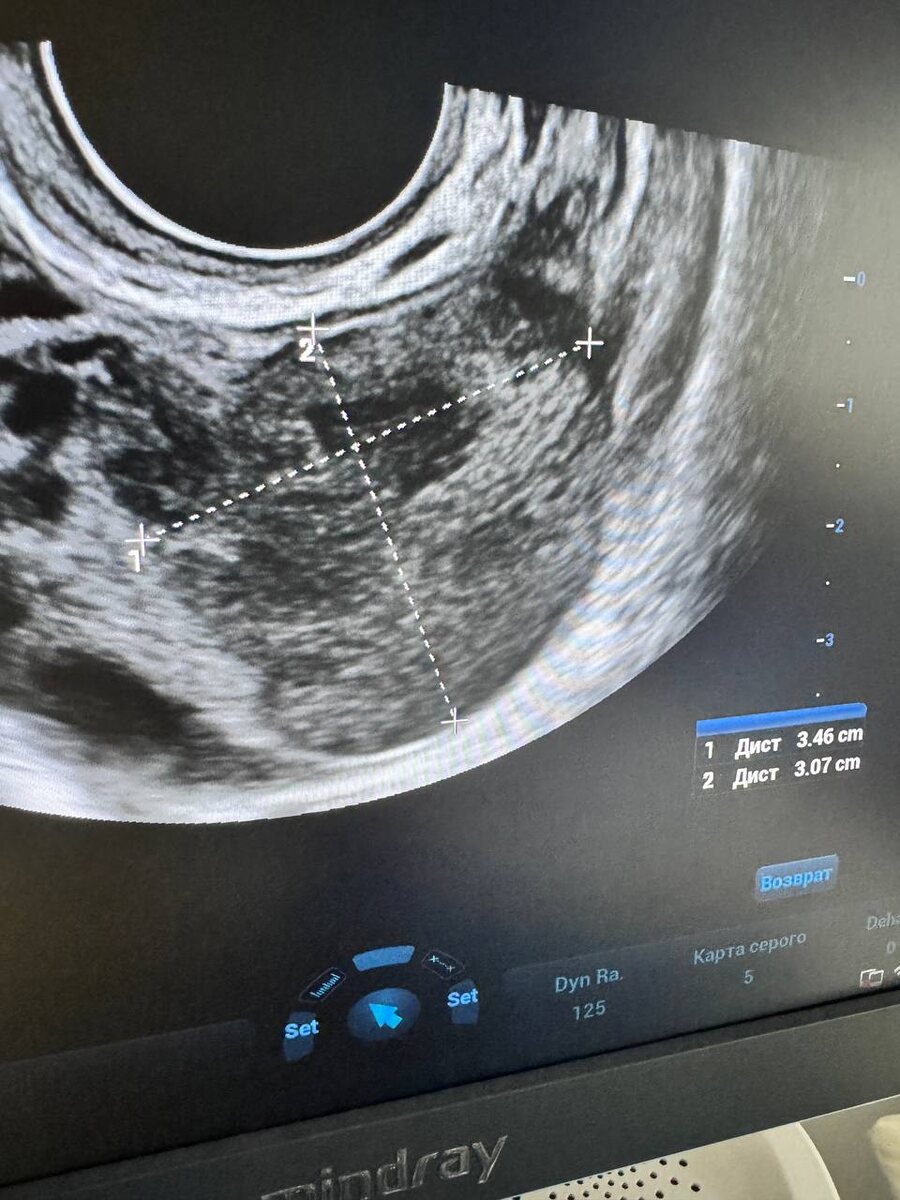

При осмотре действительно видим кисту, (фото1), правда на правом яичнике (такое бывает, иногда путаем лево-право,иногда путают стороны при написании протокола), и с первого взгляда эту кисту можно вполне принять за эндометриоидную. Но мы помним,что ВСЕ кисты нужно смотреть в динамике, приглашаем девочку в следующий менструальный цикл, и видим кисту, но совсем другого формата, она изменила свою структуру, от чего нам становится очень радостно ☺️ (фото 2).

Это дает нам право четко и твердь сказать,что киста была функциональная , она же киста желтого тела ☀️